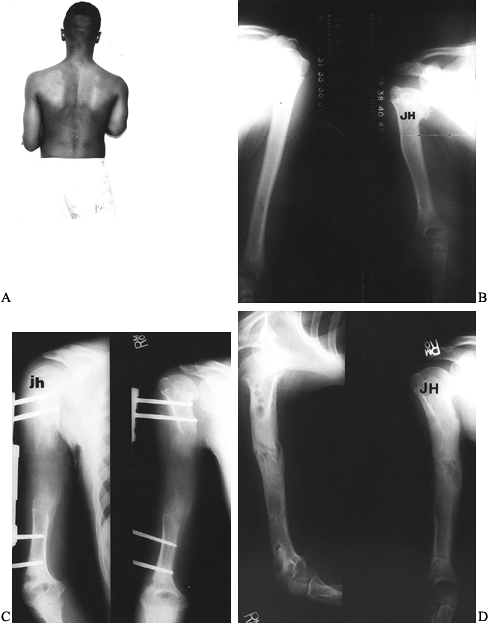

Figure 171.27. A and B:

Preoperative photographs and teleoroentgenogram of a 6-year-old boy

with congenital shortening of the femur, fibular hemimelia, and a

three-ray foot. C: The Ilizarov technique

was used for bifocal application. Acute rotational correction was

performed proximally. Elimination of distal femoral valgus and

subsequent lengthening was done distally. D and E: The photographs demonstrate symmetric internal and external rotation at the conclusion of treatment. F: Radiographs demonstrate excellent healing of both femoral and tibial lengthening sites.